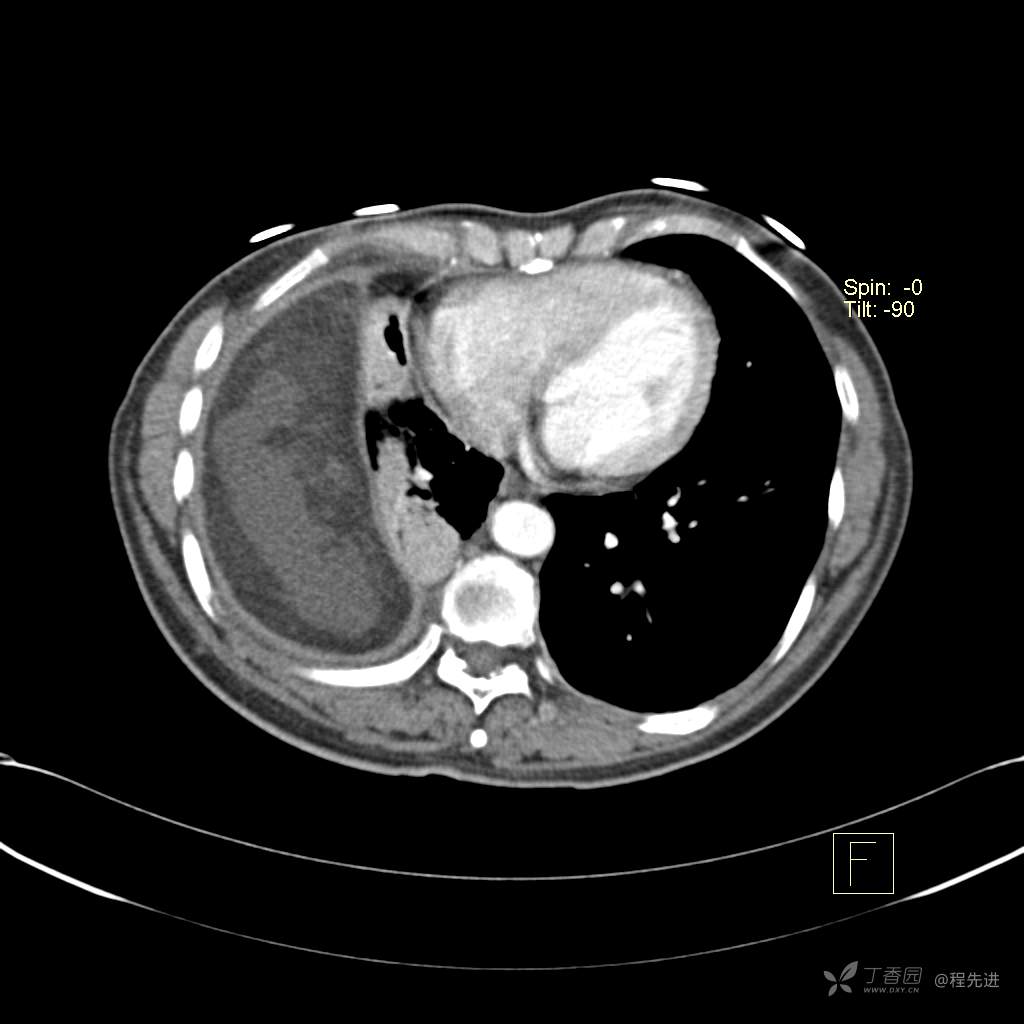

患者性别:女

患者年龄:51岁

简要病史:胸闷半年